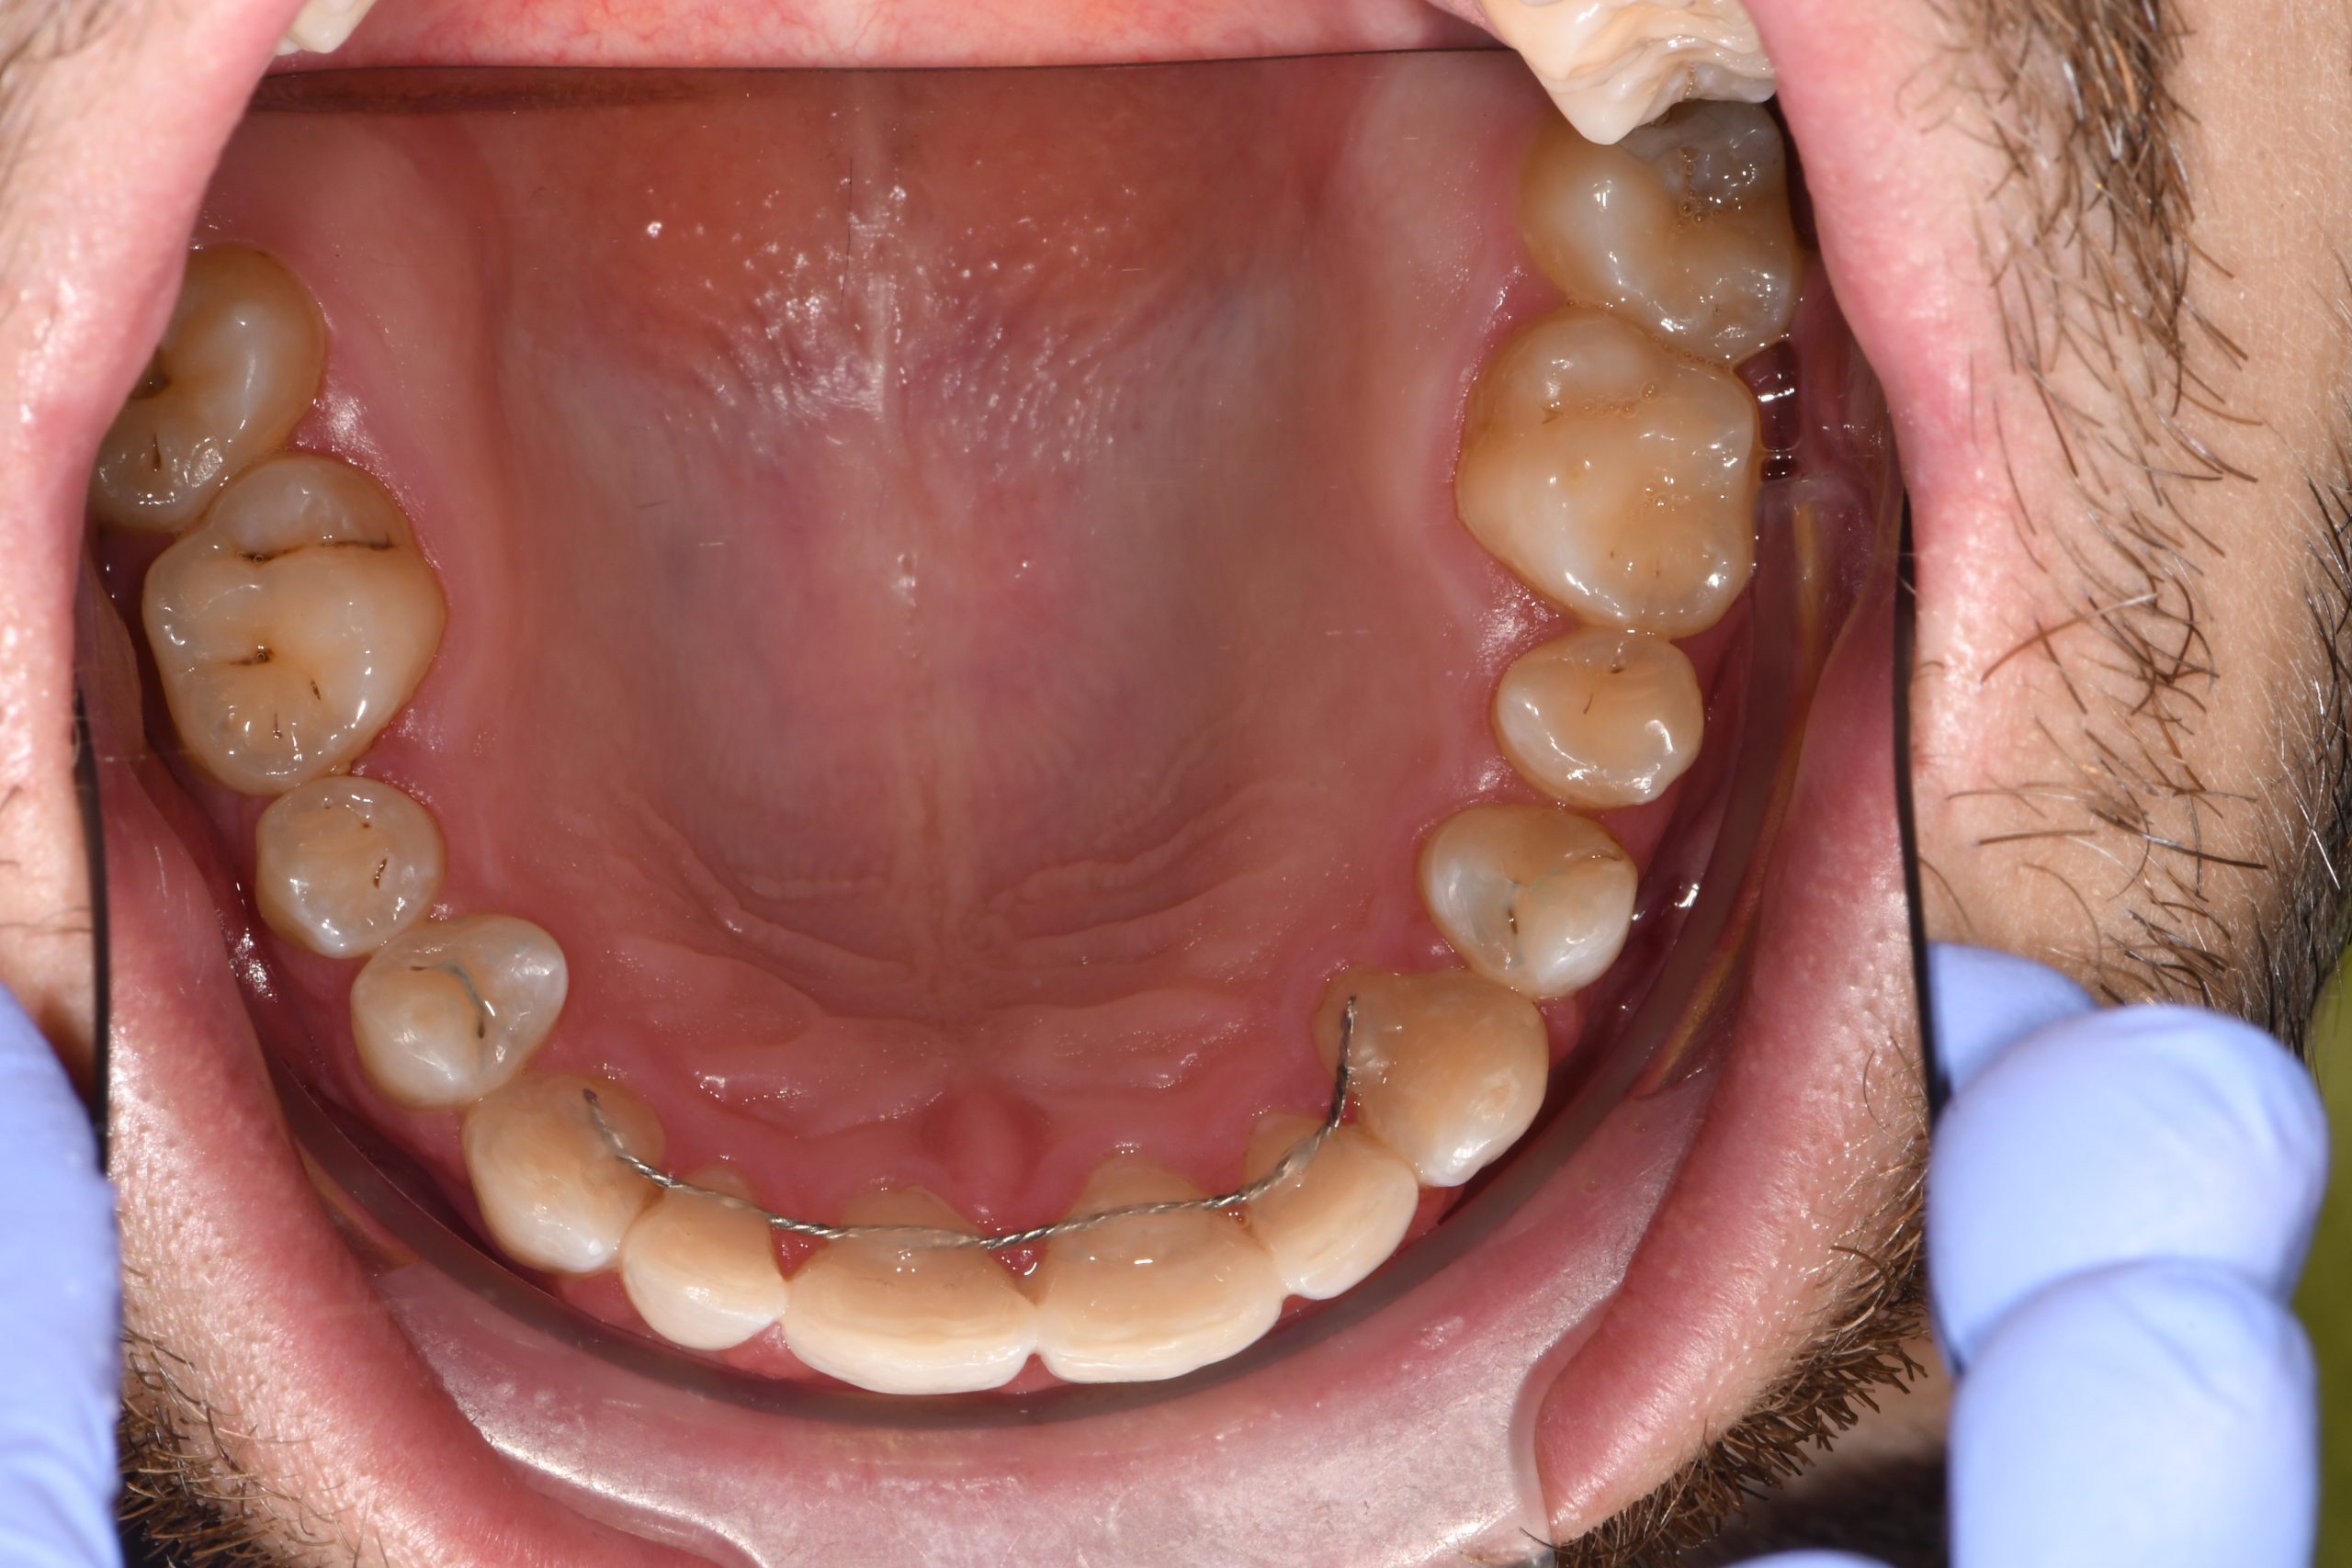

Az elmúlt évekből rengeteg szakmai referenciát tudnánk bemutatni, amelyek különböző fogszabályozási problémákat oldottak meg. Válogatva a több száz esetből, ezen az oldalon olyan képeket, információkat igyekeztünk bemutatni, amelyeknek a segítségével a jövőbeni pácienseinknek azt tudjuk üzenni: A Te fogsorod is lehet gyönyörű!